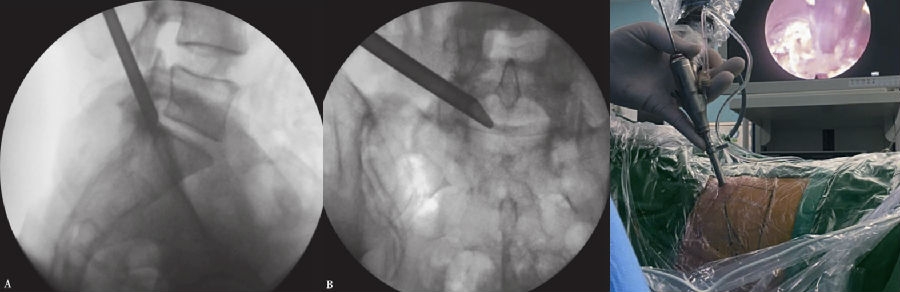

7. 置入工作套管

将7.5mm外径的工作套管置入椎间孔,并沿工作套管放入椎间孔镜。(图14、图15)

图14-图15 工作套管到位,X线片投影图显示套管头端位于椎管腔内;内镜下手术操作

A. 侧位;B.前后位

经皮内镜椎板间入路椎间盘切除术(percutaneous endoscopic interlaminar discectomy,PEID)主要用于高髂嵴和L5横突肥大的患者。PELD手术难以处理的L5~S1椎间盘突出和脱出患者。手术步骤如下:

1. 患者取俯卧位,下肢降低并屈髋、屈膝。(图26)

2. 透视定位病变节段,于后正中患侧旁开约1.0cm处按对应椎板间隙标记穿刺点(图27),术区皮肤常规消毒铺无菌巾。

3. 于穿刺点以0.5%利多卡因行局部浸润麻醉,以18G穿刺针向患侧关节突内侧及椎板间隙穿刺,根据椎间盘突出位置适当调整穿刺针在椎板间隙的位置。

4. 穿刺至黄韧带外,插入导丝,拔出穿刺针,沿进针点做7~8mm皮肤小切口,用扩张套管逐级扩张,待序列扩张后,安装工作套管(图28),与内镜及冲洗系统相连接。(图29)

图26 患者俯卧体位

图27-图30 术前透视定位;安装工作套管;连接内镜和冲洗;

内镜下磨除关节突关节下方,尽量向侧方显露